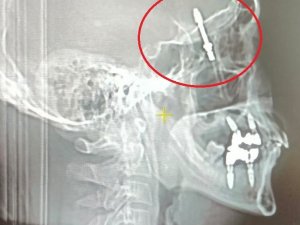

Nilüfer ilçesinde özel bir diş kliniğinde muayene olan Yılmaz'a, dişlerinin sallandığı gerekçesiyle implant tedavisi önerildi. Ancak iddiaya göre, doktor A.D.'nin hatalı müdahalesi sonucu implant vidası çene kemiğini delip kafatasına saplandı.

Baygınlık geçiren Yılmaz, kliniğin kendi aracıyla hastaneye kaldırıldı. Tomografi çekiminde vidanın beynine kadar ilerlediği ortaya çıktı. Acil ameliyata alınan talihsiz adam, saatler süren operasyonla ölümden döndü.